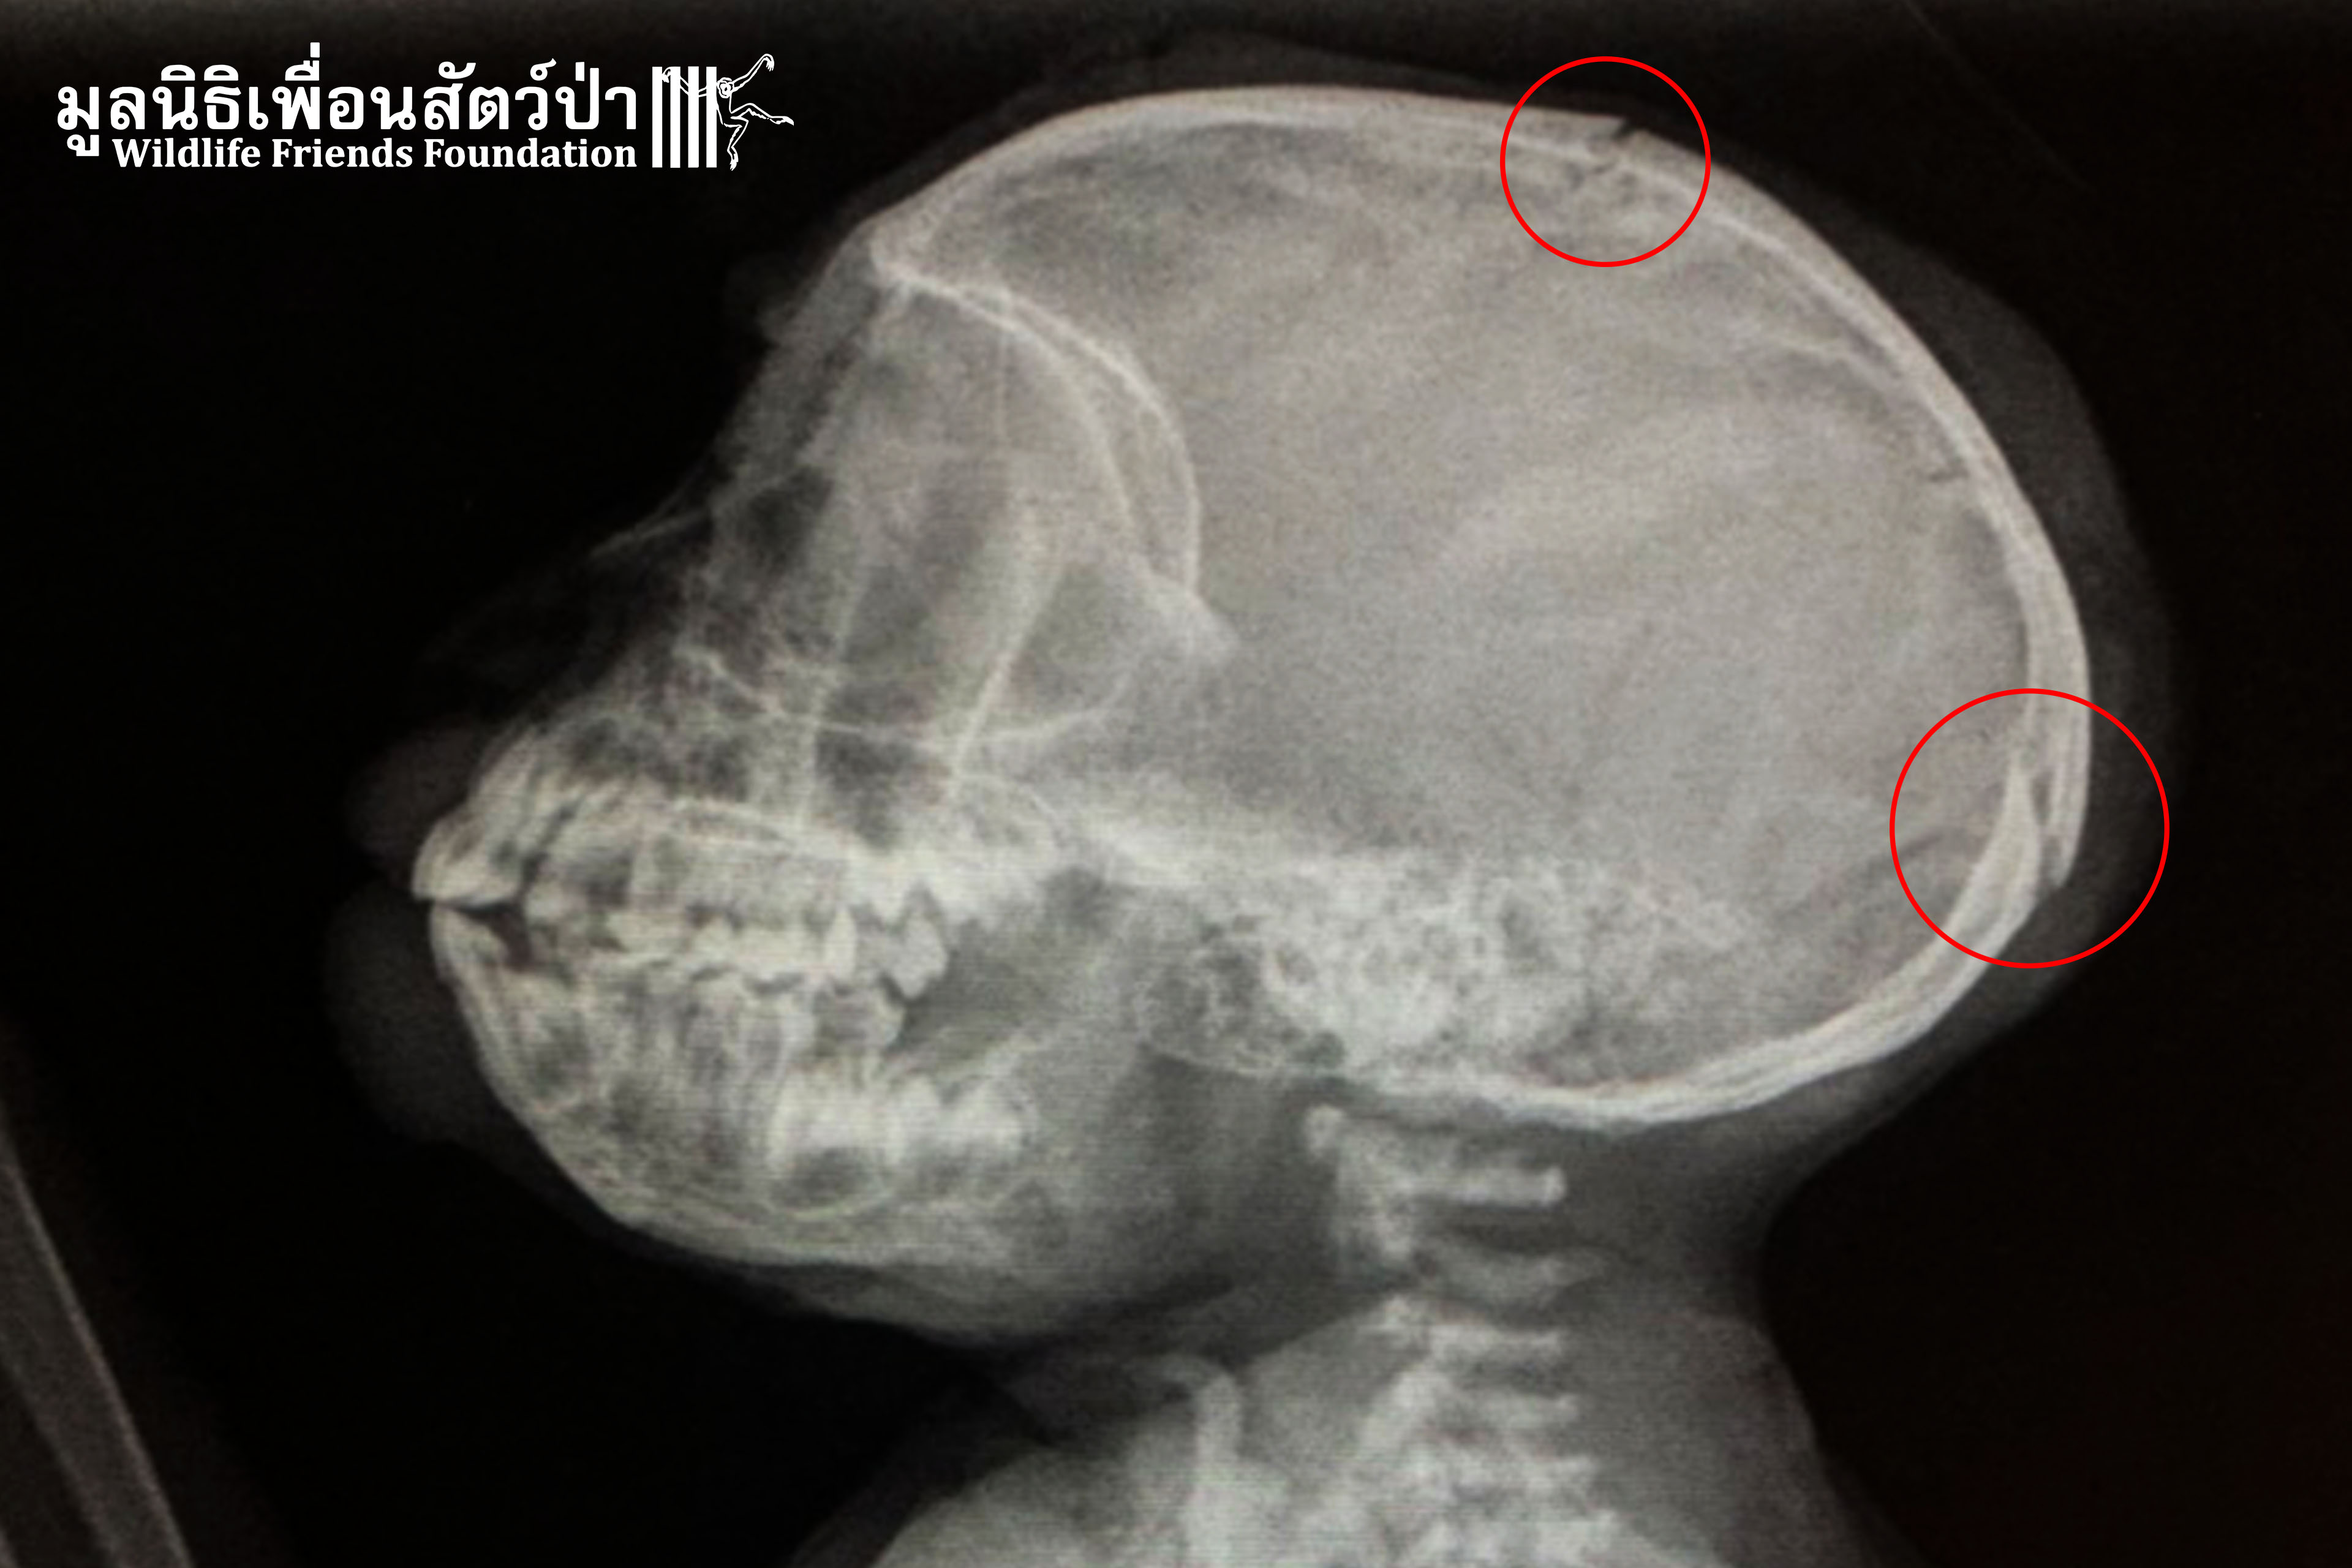

This week we received a phone call from a concerned local who found an infant Long-tailed Macaque who had been hit by a car and knocked unconscious. The WFFT Rescue Team immediately headed to rescue this poor little soul. Upon arrival, the baby monkey had already received basic first aid care and was wrapped in cloth to give him some comfort. WFFT would like to say thank you to the good citizens for doing a good deed and helping this baby. We have named him “Thor.”

Results from the X-ray examination revealed he has multiple skull fractures, but luckily other parts of the body were not broken or had any severe injuries. Overall he is still able to feed himself, which is a good sign. Thor will receive intensive care from our expert team; if he recovers from this ordeal, he will be returned to the wild. We will update you on his progress.